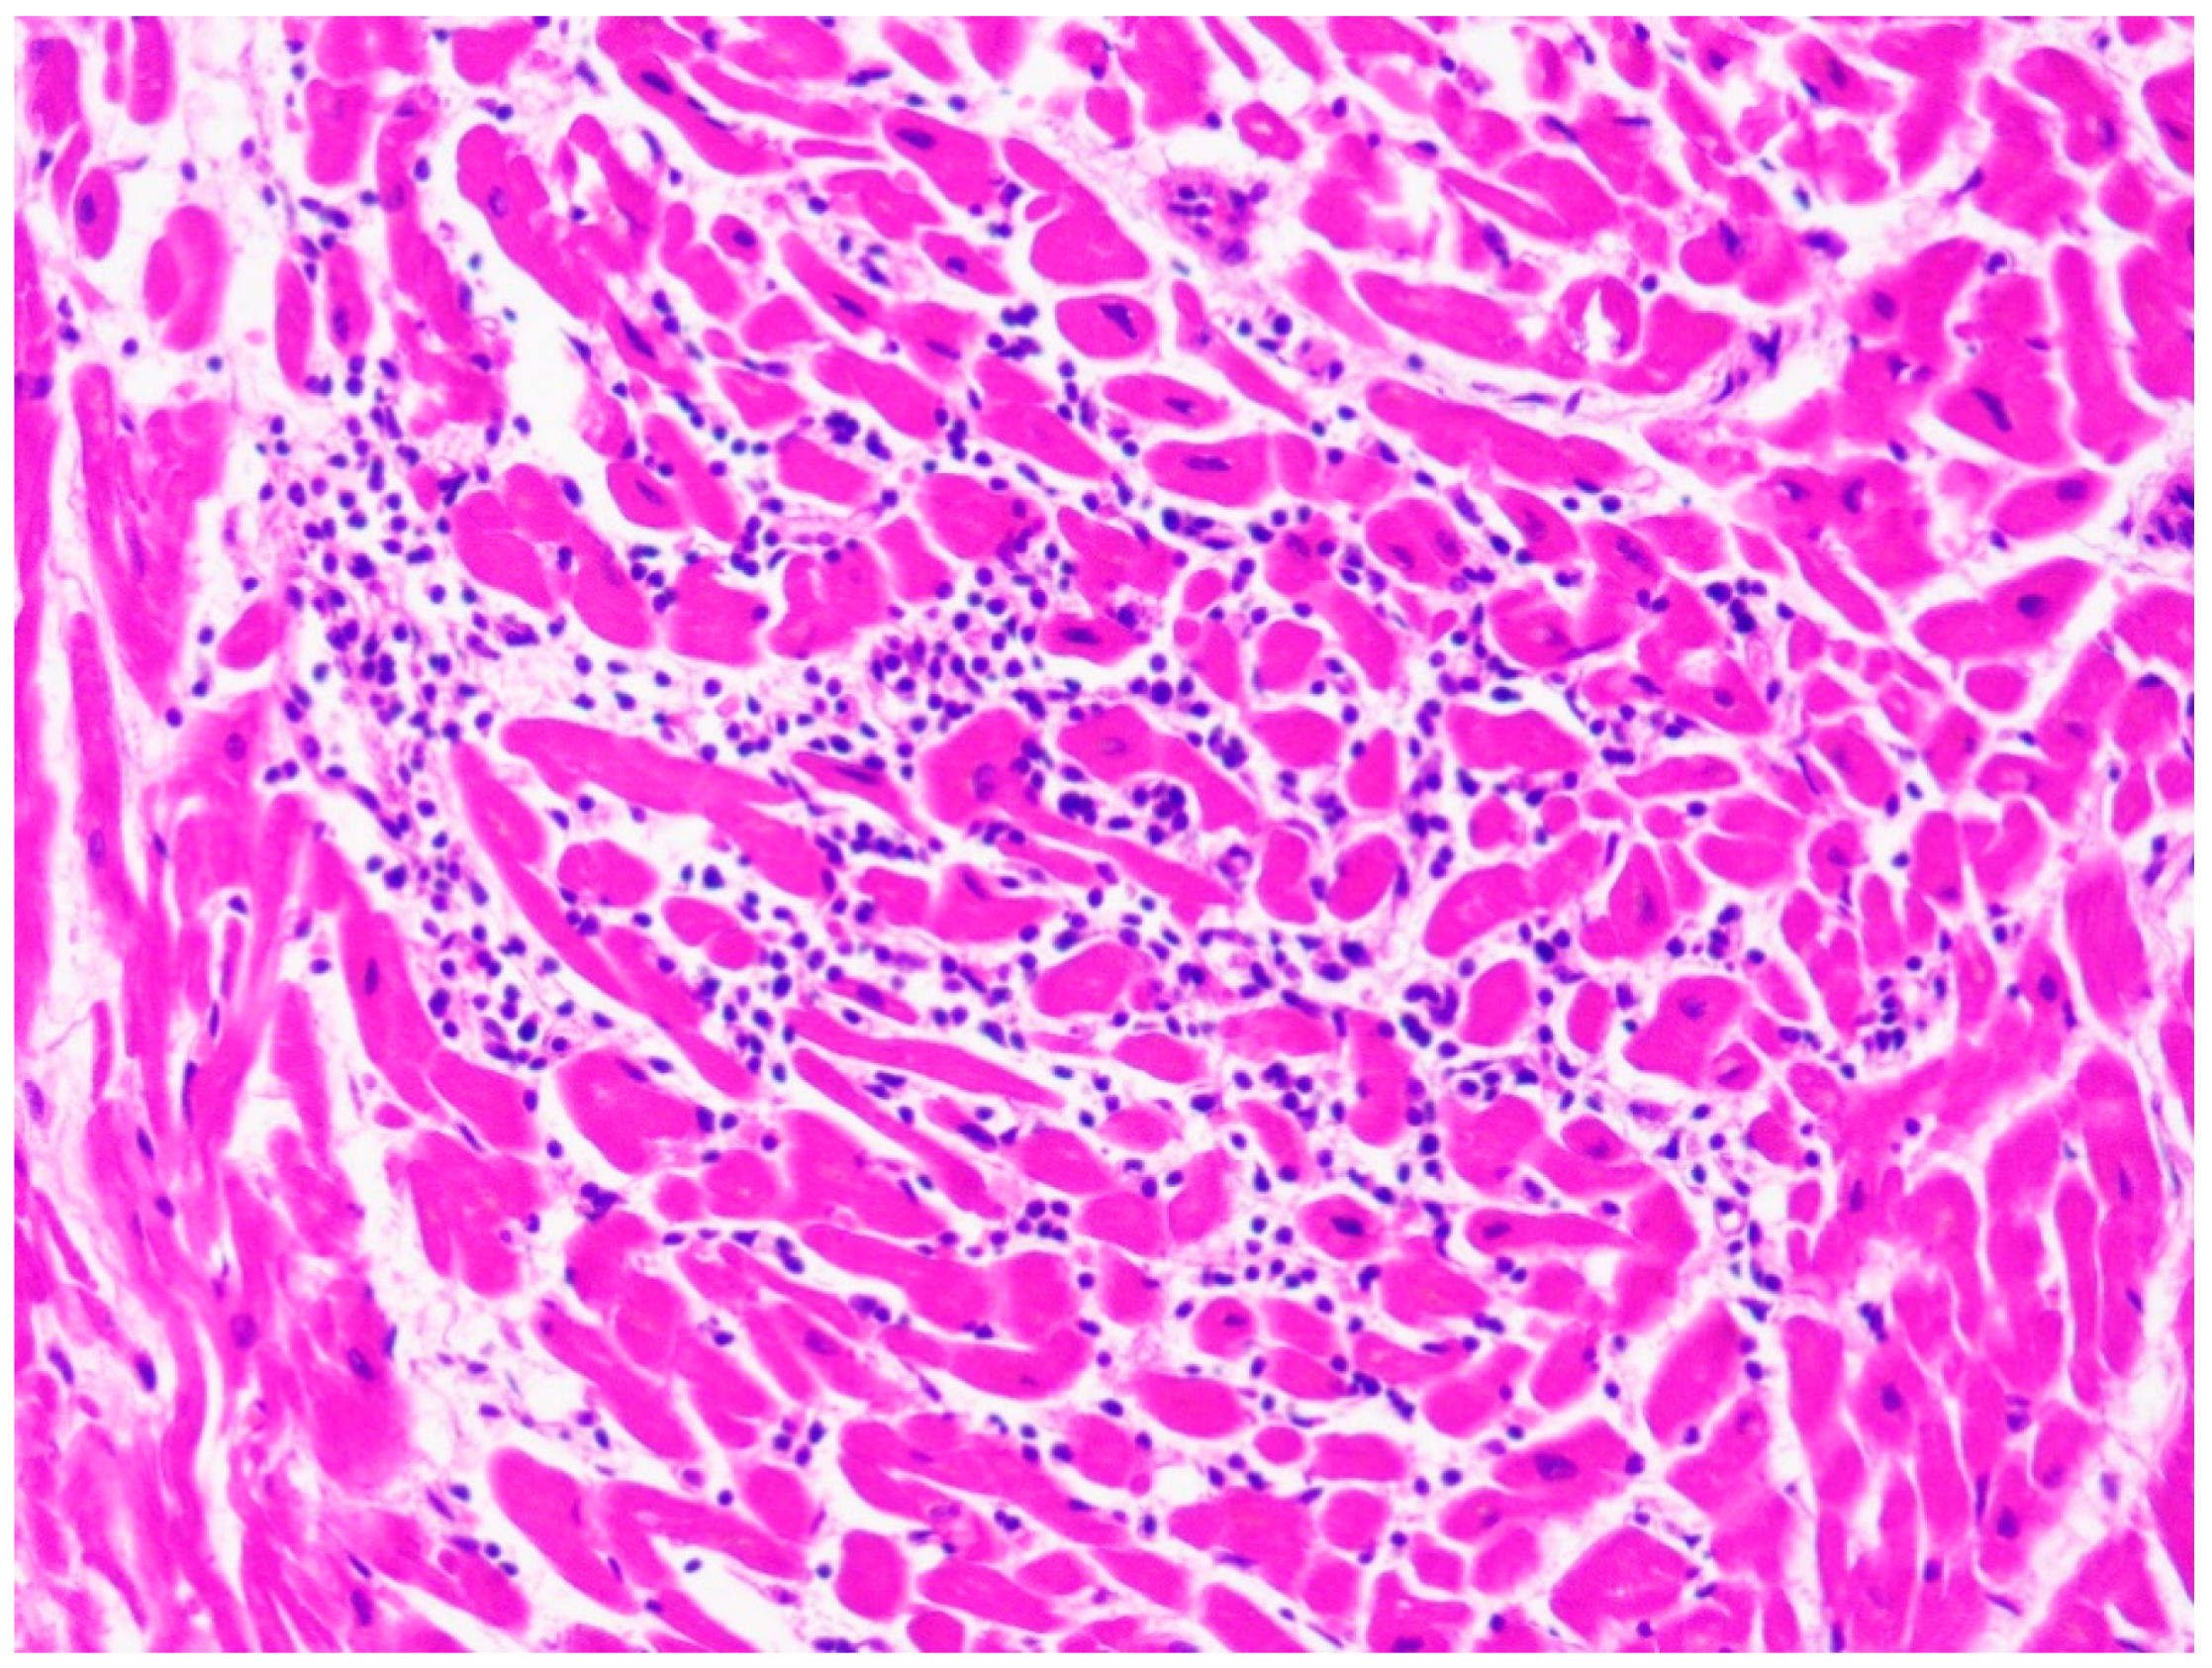

| Typical histopathological features | Myocytes hypertrophy, disarray, thickened intramural arterioles with luminal narrowing, myocardial fibrosis [102,103] | Fibrofatty replacement of the ventricular myocardium with a subepicardial-mid-mural or transmural distribution [54] | Replacement fibrosis, interstitial fibrosis, atrophied and/or hypertrophied cardiomyocytes, nuclear pleomorphism [82] |